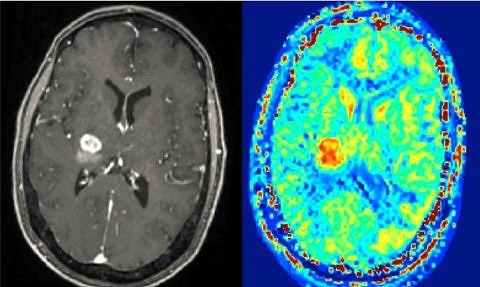

Oberarzt erhielt Dagmar-Eißner-Preis 2021 Dr. Christian Schmidkonz von der Nuklearmedizinischen Klinik (Direktor: Prof. Dr. Torsten Kuwert) des Universitätsklinikums Erlangen gewann 2021 seinen vierten Forschungspreis für das Uni-Klinikum Erlangen: Die Mittelrheinische Gesellschaft für Nukl...